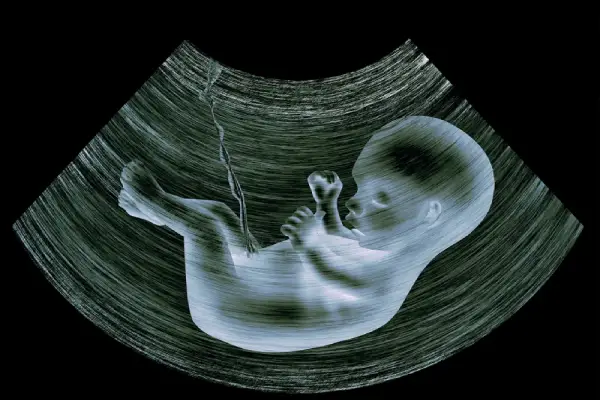

Pregnancy Ultrasound (Antenatal Scan)

Regular check-up for fetal growth, heartbeat, and well-being. Widely recommended throughout pregnancy for monitoring development.

3D/4D Ultrasound in PCMC

Advanced imaging that provides a realistic view of the fetus. Preferred for detailed prenatal assessment and bonding with your unborn baby.